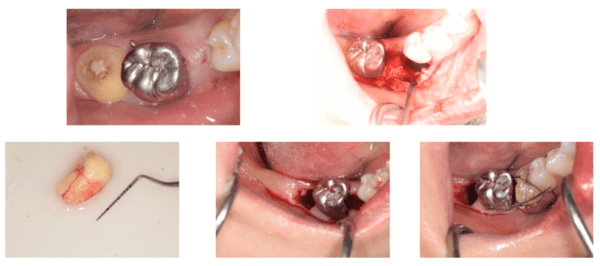

手術前

手術中

説明:

歯ぐきを切り、骨の状態を確認します。移植する歯が入るためのスペースを作るために、骨を歯が入るように削っていきます。

移植する歯

骨のスペースを確保したら移植する歯を抜きます。

移植した歯

移植した歯のレントゲン写真

移植した歯の写真です。隣の歯とワイヤーで固定します。約3週間でワイヤーは外します。